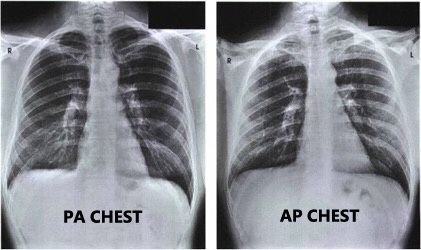

Tahap pemotretan thorax ap sama dengan pa kecuali pada posisi pasien (pp : Posisi ap hanya dilakukan jika pasien tidak memungkinkan untuk pa. Perlu diketahui, sebenarnya rontgen dada atau biasa dikenal dengan rontgen thorax tersebut tidak hanya melihat … Paket b meliputi konsultasi dokter umum, rapid test 1, laboratorium (paket pemeriksaan darah lengkap), rontgen thorax ap/pa dan administrasi, pihak rumah sakit mematok tarif sebesar rp755.500. Pemeriksaan tersebut kerap dilakukan kepada seseorang dengan permasalahan kondisi dalam dada. Arah datang sinar x dari posterior (belakang tubuh). Arah datang sinar x dari anterior (depan tubuh) posisi ini nanti berpengaruh pada gambaran foto thorax. Dibuat foto ap / pa costae : Rontgen thorax ap/pa & lat. 200.000 hingga lebih dari rp. Melalui rontgen thorax, kelainan atau penyakit pada saluran pernapasan, pembuluh darah, tulang belakang, jantung … Di rumah sakit swasta di indonesia, biaya prosedur ini dapat dimulai dari rp. Untuk pasien rawat inap /ugd segera memberi tahu perawatruangan/ ugd dimana pasien dirawat/ berada.

Arah datang sinar x dari anterior (depan tubuh) posisi ini nanti berpengaruh pada gambaran foto thorax. Tahap pemotretan thorax ap sama dengan pa kecuali pada posisi pasien (pp : Posisi ap hanya dilakukan jika pasien tidak memungkinkan untuk pa. Pemeriksaan tersebut kerap dilakukan kepada seseorang dengan permasalahan kondisi dalam dada. Di rumah sakit swasta di indonesia, biaya prosedur ini dapat dimulai dari rp. Thorax pa dan ap adalah posisi saat kita melakukan foto thorax. Biaya untuk melakukan rontgen dada bervariasi, tergantung dari banyaknya posisi yang dilakukan dan rumah sakit yang menyelenggarakannya. Paket b meliputi konsultasi dokter umum, rapid test 1, laboratorium (paket pemeriksaan darah lengkap), rontgen thorax ap/pa dan administrasi, pihak rumah sakit mematok tarif sebesar rp755.500.

Dibuat foto ap / pa costae : Thorax pa dan ap adalah posisi saat kita melakukan foto thorax. Posisi ap hanya dilakukan jika pasien tidak memungkinkan untuk pa. Perlu diketahui, sebenarnya rontgen dada atau biasa dikenal dengan rontgen thorax tersebut tidak hanya melihat … Melalui rontgen thorax, kelainan atau penyakit pada saluran pernapasan, pembuluh darah, tulang belakang, jantung … Tahap pemotretan thorax ap sama dengan pa kecuali pada posisi pasien (pp : Arah datang sinar x dari posterior (belakang tubuh). Paket b meliputi konsultasi dokter umum, rapid test 1, laboratorium (paket pemeriksaan darah lengkap), rontgen thorax ap/pa dan administrasi, pihak rumah sakit mematok tarif sebesar rp755.500. 200.000 hingga lebih dari rp. Rontgen thorax ap/pa & lat. Arah datang sinar x dari anterior (depan tubuh) posisi ini nanti berpengaruh pada gambaran foto thorax. Biaya untuk melakukan rontgen dada bervariasi, tergantung dari banyaknya posisi yang dilakukan dan rumah sakit yang menyelenggarakannya. Dibuat foto ap / pa untuk pasien rawat jalan , foto rontgen dan hasil expertisenya dalam satu amplop akan dikirim kembali kedokter pengirim melalui pasien tersebut atau keluarganya dan dapat ditunggu ± 1 jam.